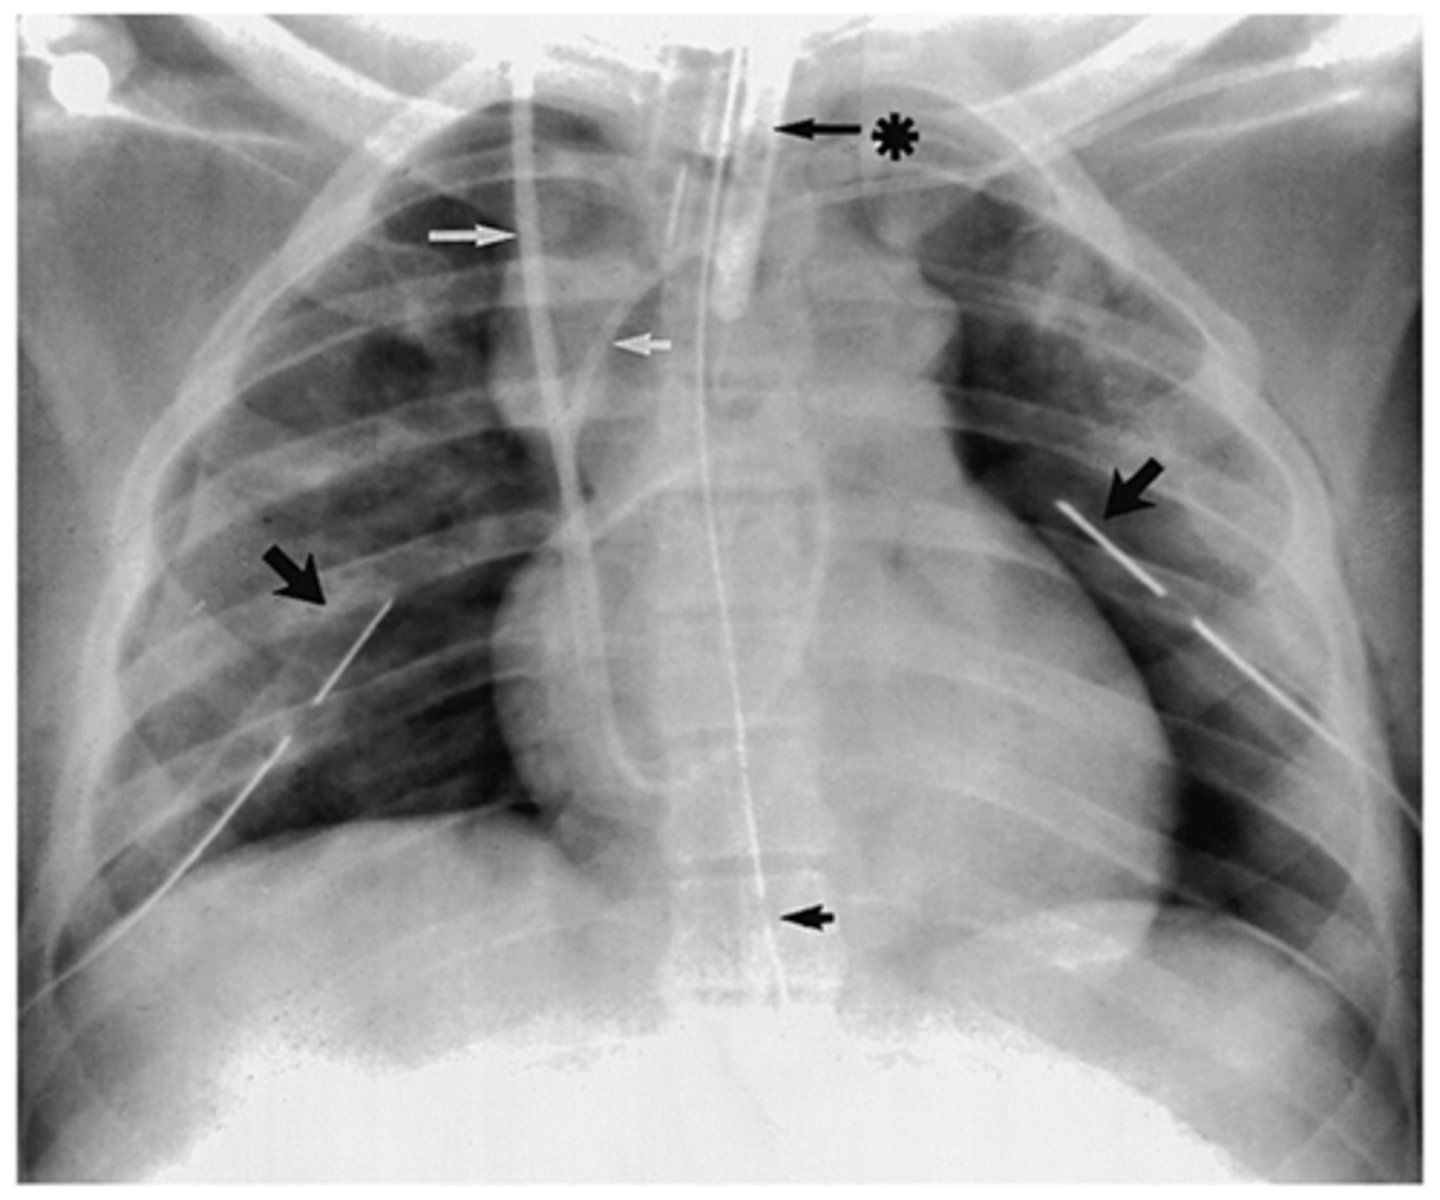

CXR of tracheal intubation with ETT

What is going on in this CXR?

Pulmonary artery catheter (tip at right midlung near hilum)

What is goin going on in this CXR?

Nasogastric feeding tube (NG tube) placement (ensure tip places at stomach or small bowel)

What is goin going on in this CXR?

Chest tube (tip of tube should be posterior and near apex of lung for drainage)

What is goin going on in this CXR?